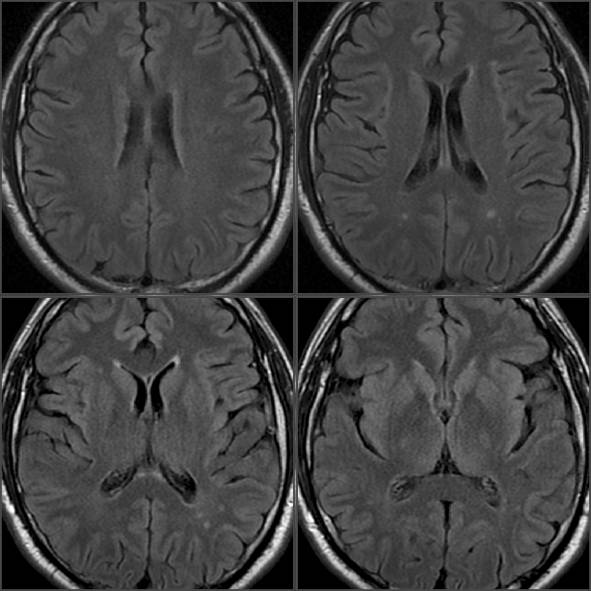

Follow-up MRI

(2013) revealed indirect signs of intracranial hypertension: enlarged perioptic

subarachnoid spaces without cerebral cavity expansion; there were no signs of

brain atrophy. Within the white matter of the brain (posterior watershed zone),

both on the right and on the left sides (Fig. 1, 2), T2 / FLAIR hyperintense

small foci, located in the juxtacortical, subcortical and deep white matter

areas (the border zone) have been found; another similar focus has been visualized

juxtacortical in the front insular region on the left. The foci were rounded or

spindle-shaped with the radial type of location perpendicular to the boundaries

of the lateral ventricles. There were no signs of pathological accumulation of

gadolinium - containing contrast agent after its administration. The number of

foci as well as their sizes and shapes did not undergo any significant

transformation. Due to cumulative signs the referred foci probably belong to

the perivascular domain, suggesting infectious / inflammatory etiology for

these lesions [3].

Fig. 1

Supratentorial axial T2 FLAIR - weighted, slice thickness 5 mm.